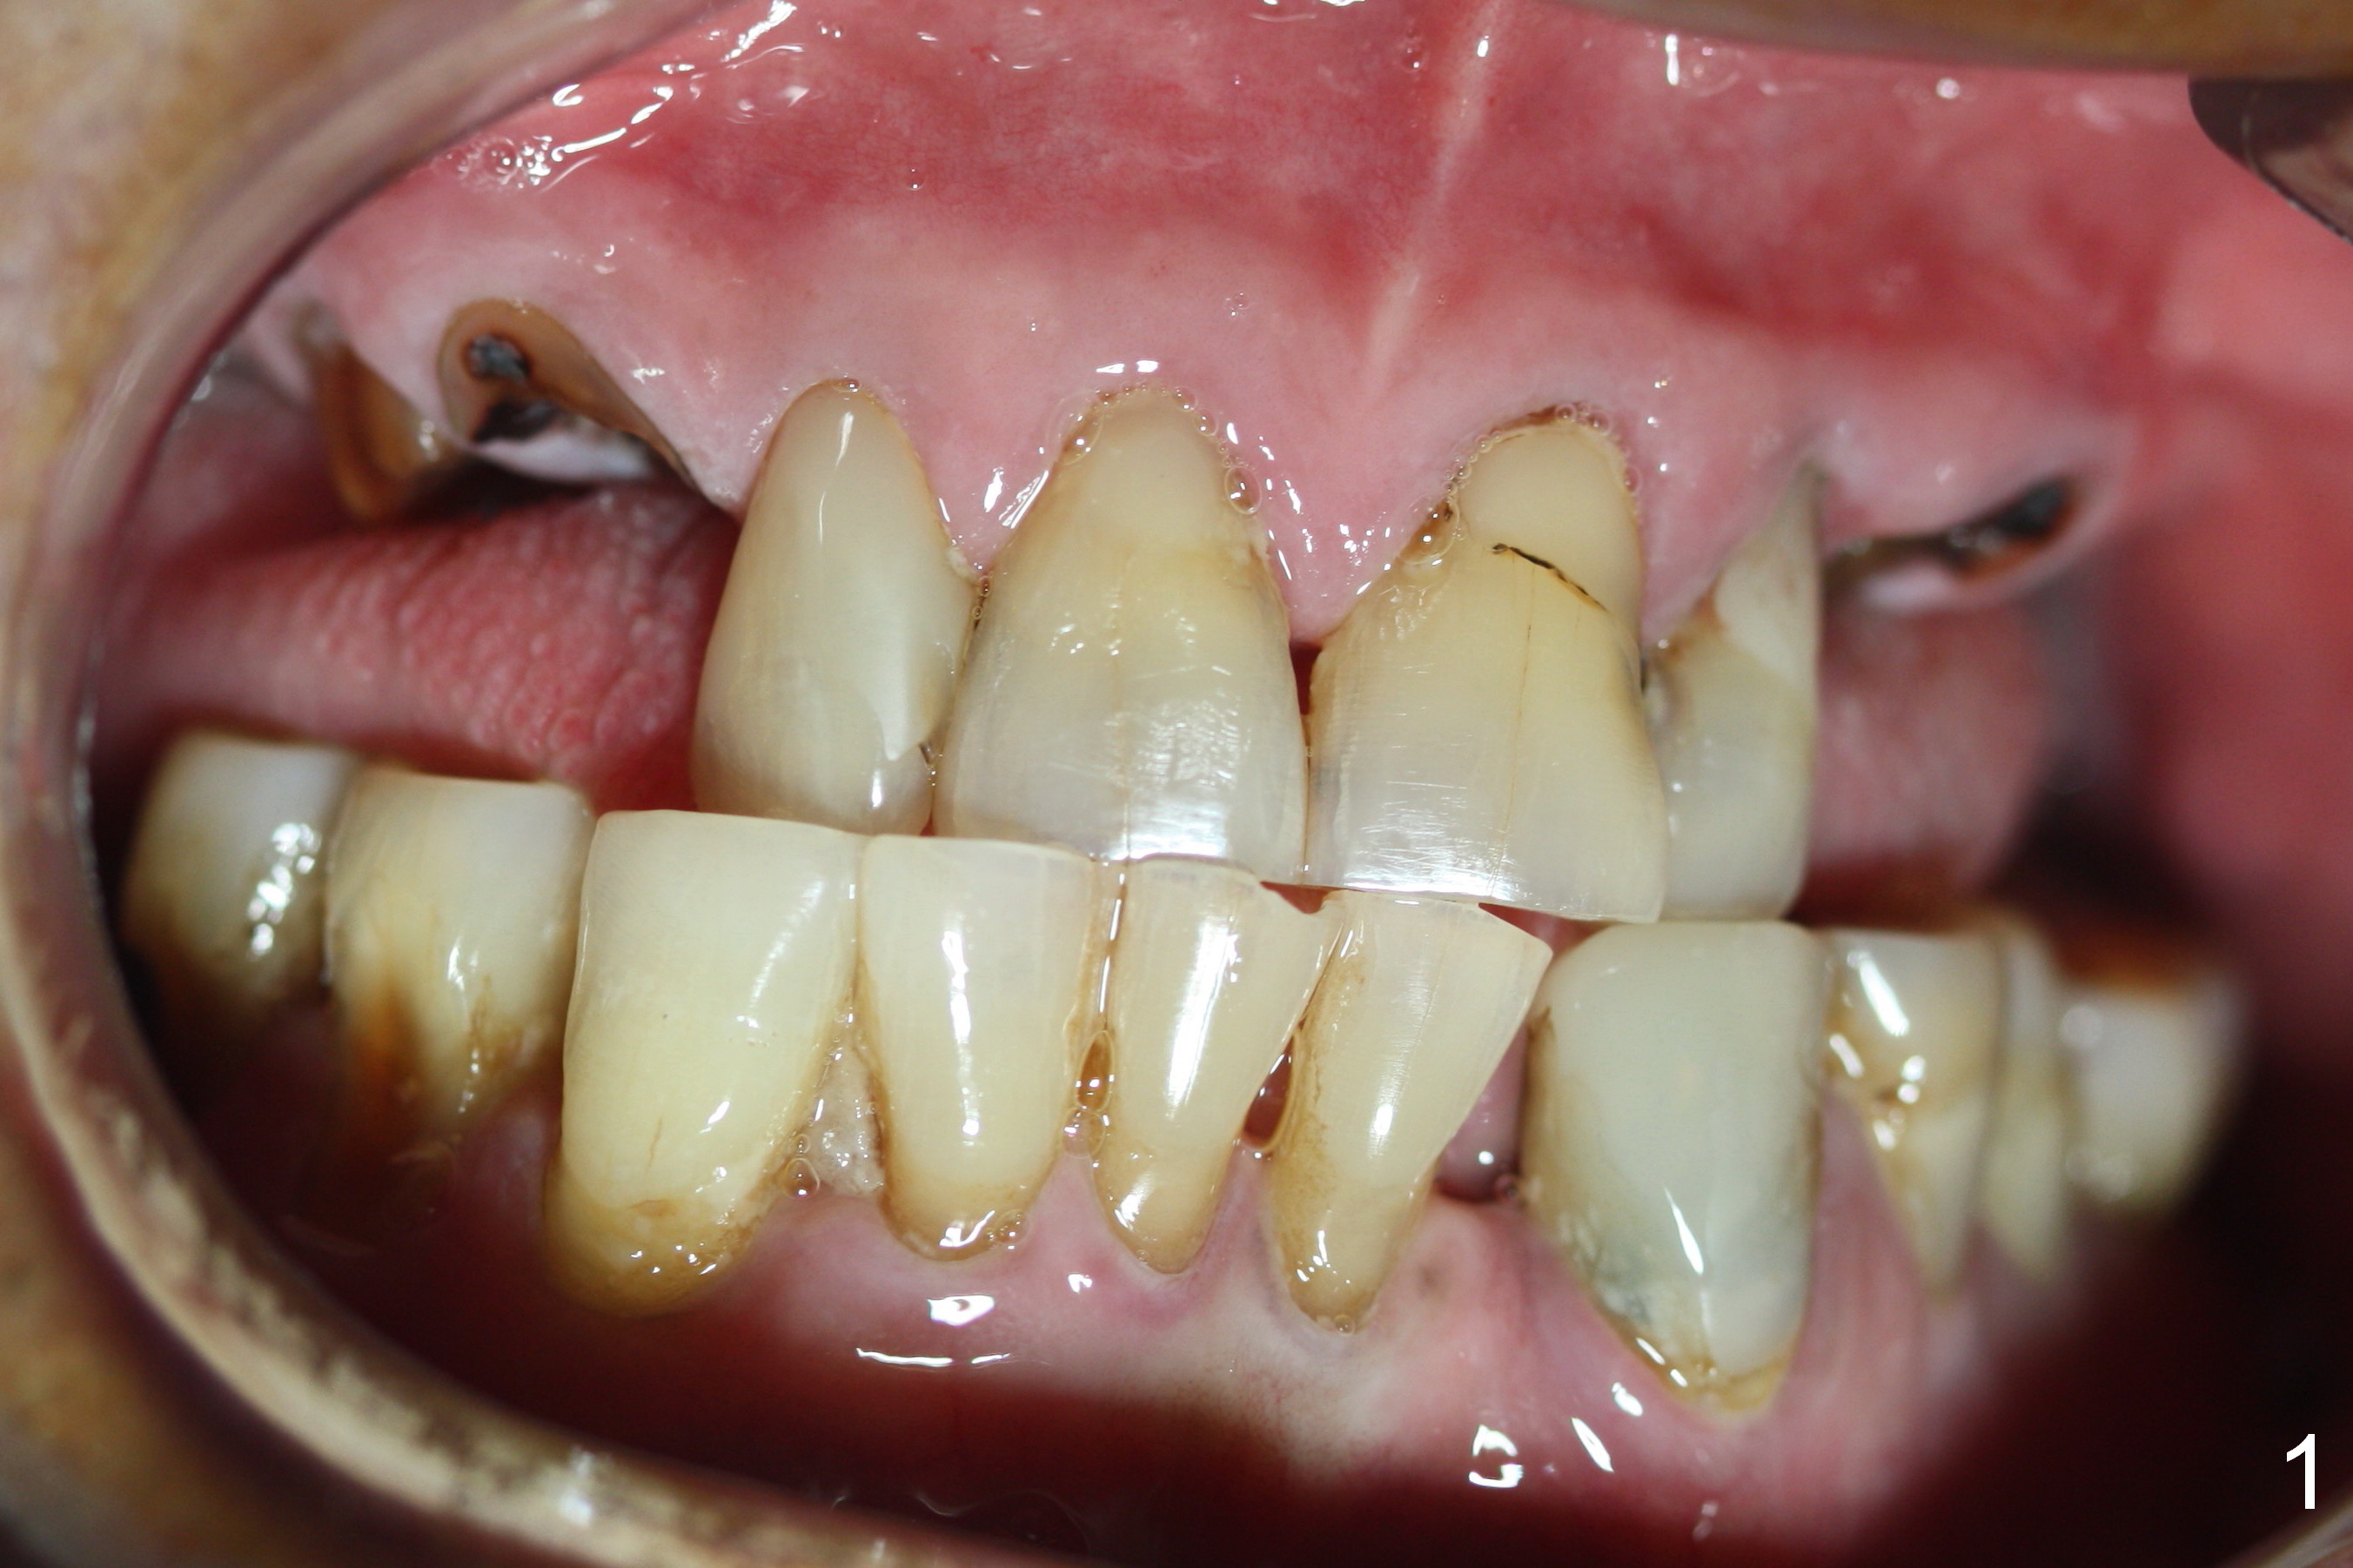

Several of CK's upper teeth (apparently in cross bite) are to be restored with implants (Fig.1).  The first two are #5 and 6; note the oval roots (Fig.2).  After extraction, and curettage, osteotomy starts in the palatal aspect of each socket.  The 1st intraop PA shows that the trajectory at #6 is incorrect (Fig.3).  After adjustment, osteotomies look parallel (Fig.4: D: 3.5x20 mm drill; T: 4.5x20 mm tap).  This suggests how important it is to use parallel pins to check initial osteotomies for neighboring implants (Fig.3).  The trajectory of the implants remains acceptable (Fig.5: 4.5x20 mm with insertion torque »60 Ncm); so is the position of the implants (as palatal as possible; Fig.6 (*: bone graft)).   Immediate provisionals are fabricated in cross bite.